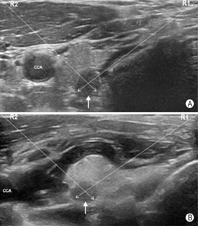

如图19所示,对于气管近旁尤其是2~5点钟位(以甲状腺横切面为参照表盘,于对侧腺体则应是7~10点钟位)的目标结节,穿刺操作宜选用由内向外穿刺法,同时操作者可使用液体隔离技术使目标病灶向外侧移位,增大端侧式穿刺进针的角度,以规避气管壁对穿刺针尖的阻碍,并改善穿刺针尖的显示清晰度。如图20所示,对于位于7~10点位(对侧腺体应是2~5点位)邻近颈总动脉的病灶,也宜选用由"内向外"穿刺法。同样,操作者也可采用液体隔离方法使得颈总动脉向外侧移位,增大目标病灶与颈总动脉之间的距离,避免误伤颈总动脉。

专家意见:液体隔离法技术可促使甲状腺结节或甲状腺周围毗邻结构移位,优化穿刺路径,营造安全操作空间。